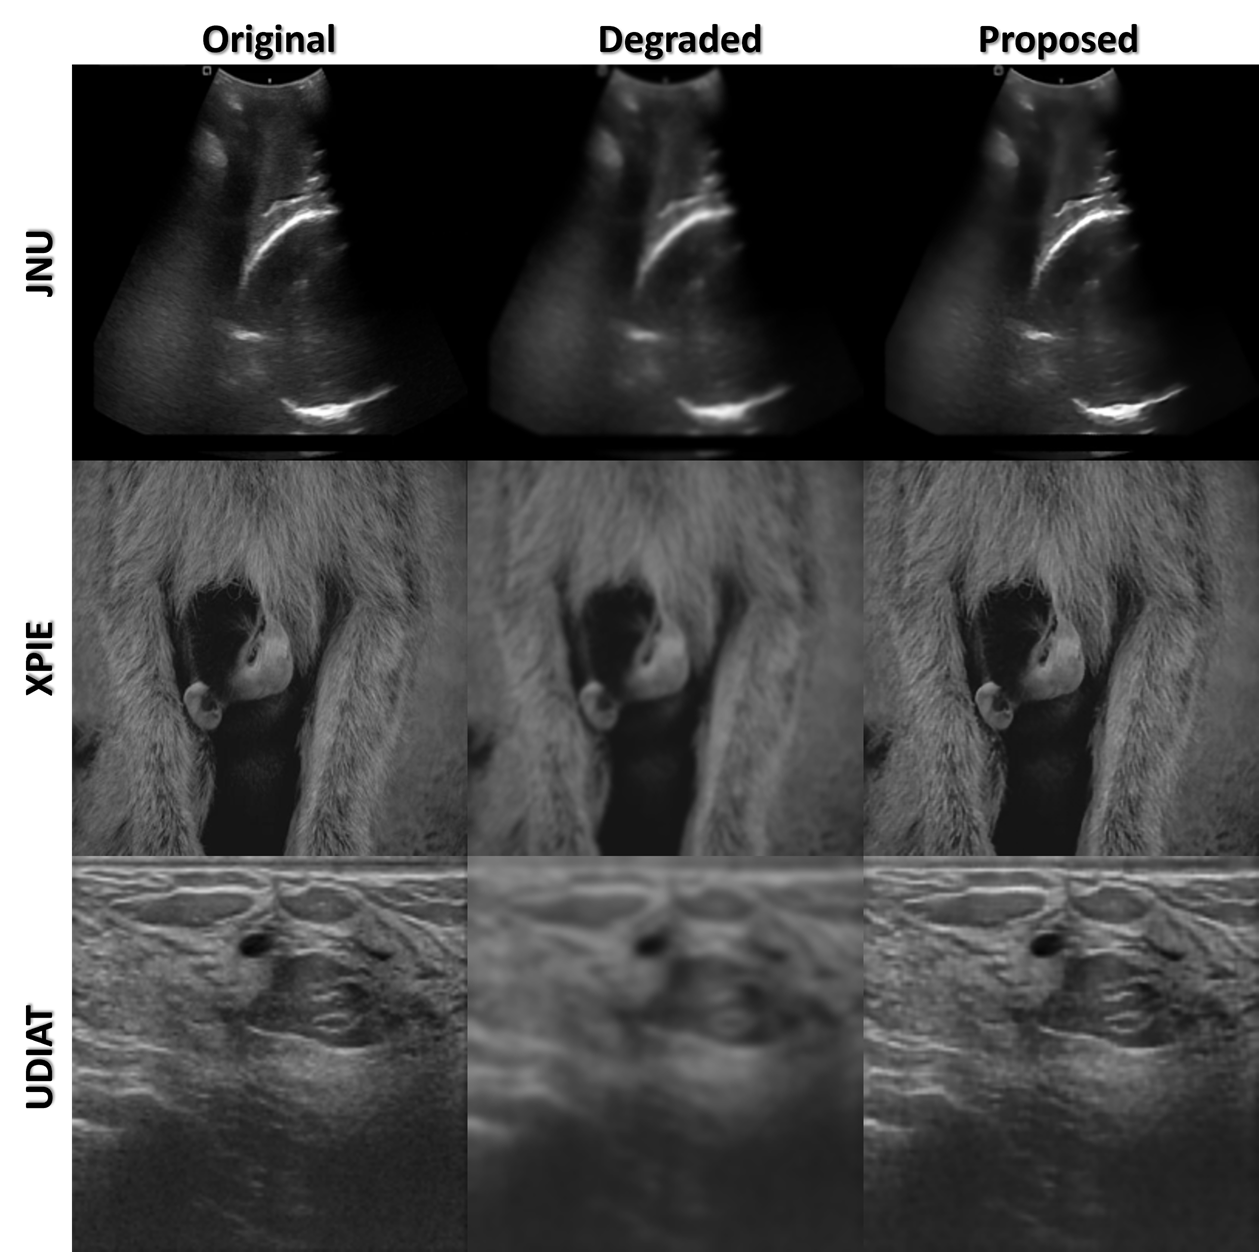

Figure 6: Single-level comparison (blur level σ=7\sigma{=}7) across datasets showing original, blurred, and proposed deblurred outputs.

Figure 6 shows single-level (σ=7\sigma{=}7) examples across JNU, UDIAT, and XPIE, where proposed method visibly restores edges and suppresses speckle-like texture. Table 2 summarizes PSNR/SSIM vs. blur level for inputs and proposed outputs across datasets. Gains are consistent from mild to severe blur, indicating robustness to PSF variation.

Quantitative gains. Across the blur ladder (σ{3,,15}\sigma\!\in\!\{3,\dots,15\}) and all five datasets, the proposed method raises PSNR by +3.56 to +13.78 dB and SSIM by +0.01 to +0.26 (Table 2). At the operating point used in Fig. 6 (σ=7\sigma{=}7), the mean improvement over all datasets is +9.07 dB PSNR and +0.118 SSIM, with per–dataset gains: JNU (+8.62 dB / +0.05), UDIAT (+8.50 dB / +0.24), XPIE–Object (+8.30 dB / +0.15), XPIE–Mask (+12.74 dB / +0.03), and PSFHS (+7.21 dB / +0.12). The largest PSNR uplift occurs on XPIE–Mask at severe blur (σ=15\sigma{=}15: +13.78 dB), while the largest SSIM gains are on UDIAT (up to +0.26 for σ9\sigma\!\geq\!9). Overall, improvements persist from mild to heavy blur, and they increase relatively as blur severity grows, indicating robustness to PSF variation and consistent recovery of both fidelity (PSNR) and perceptual structure (SSIM).